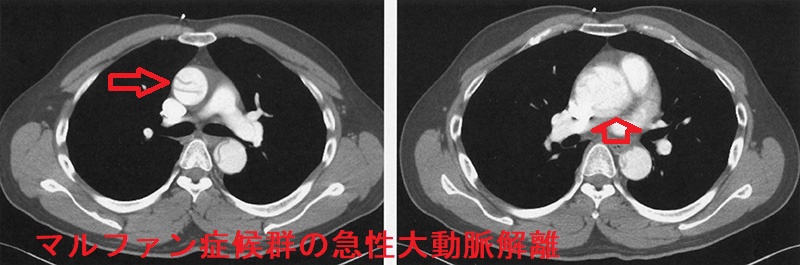

マルファン症候群(marfan syndrome:MFS)は、常染色体優性遺伝性の結合組織異常。フィブリリン-1(fibrillin-1)をコードするFBN1遺伝子やTGF-β 受容体遺伝子の突然変異が原因で、過剰TGF-βの臓器沈着からコラーゲン形成障害が生じます。

マルファン症候群の身体的特徴として、高身長で四肢の指が長い、胸郭の変形、眼の水晶体亜脱臼などがあります。

マルファン症候群で特に問題となるのが大動脈壁の脆弱性で、

- 大動脈弁輪拡張による大動脈弁閉鎖不全症(AR)

- 大動脈瘤、急性大動脈解離がおきると命にかかわる

通常の急性大動脈解離は60歳以上の高齢者に多いが、マルファン症候群では20歳-30歳代に発症することが多い。激しい運動はマルファン症候群の脆弱な動脈壁を破綻させるため禁忌。

マルファン症候群の急性大動脈解離 胸部造影CT 水平断像;矢印はflap